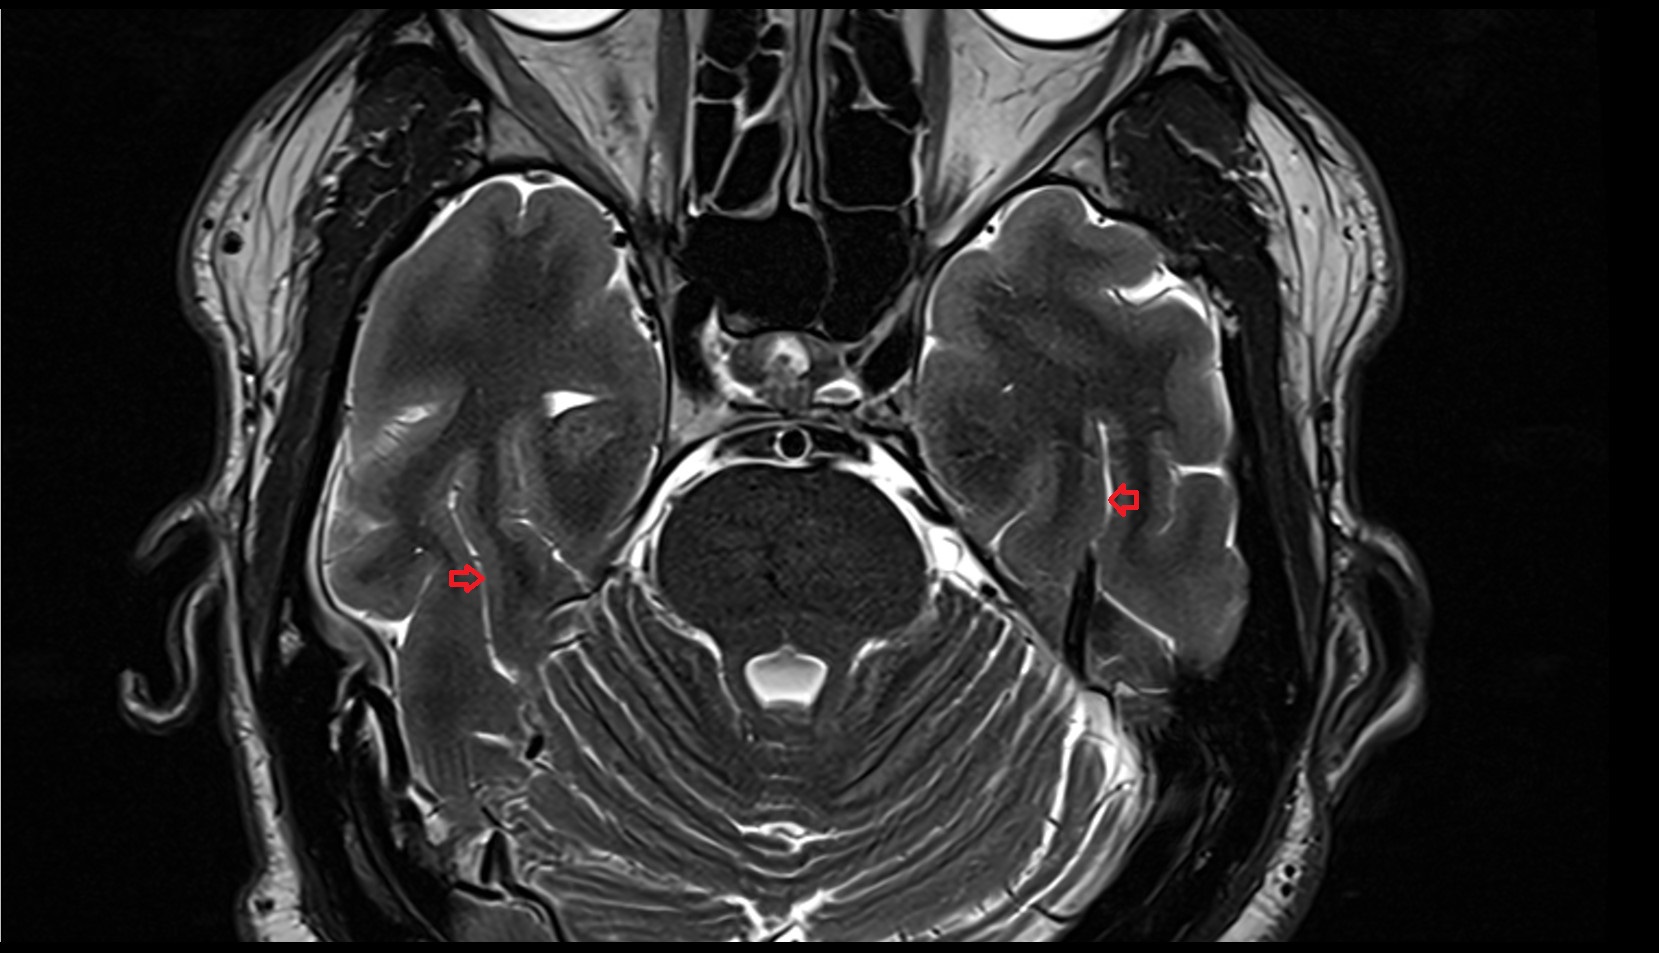

- Hippocampal body

- Hippocampal head

- Hippocampal tail

- Body of hippocampus

- Head of hippocampus

- Tail of hippocampus

- Hippocampus